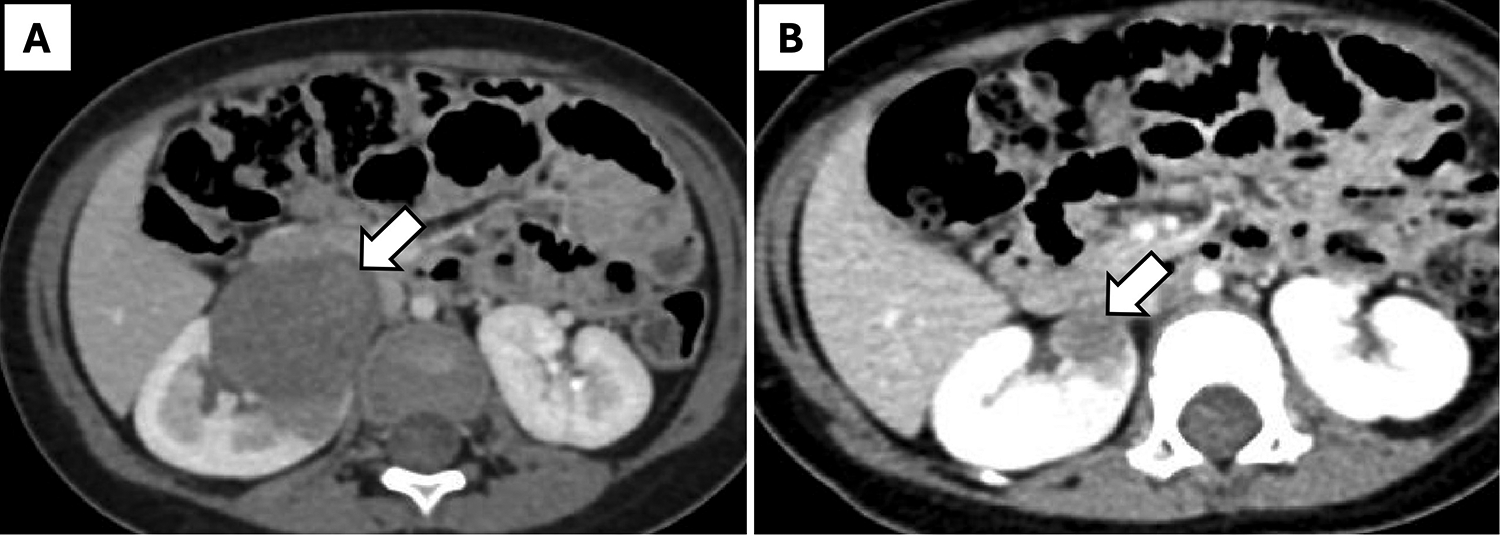

Figure 2

A 12-month-old girl with WAGR syndrome and right-sided Wilms' tumor. (A) Pre-chemotherapy axial CT scan showing a large renal mass (arrow). (B) Post-chemotherapy axial CT scan demonstrating regression of the mass (arrow).

Nephrectomy was performed after tumor shrinkage to the proposed maximum diameter on contrast-enhanced computed tomography (CECT) scan, achieved within 4 cycles of neoadjuvant chemotherapy in all cases. R0 resection was accomplished in all cases, with tumor sizes ranging from 1.9 cm × 1 cm × 1 cm to 6 cm × 5 cm × 5 cm. Eight children with renal tumor had classical WT, while one girl (aged 7 years, weight 43 kg) had a cystic partially differentiated WT of the upper pole of the left kidney and underwent partial nephrectomy. Robotic surgery was completed successfully in 7 out of 9 patients without complications, with a median operative time of 128 min (range: 102–150 min). Estimated blood loss ranged from 10 to 105 ml, with a median of 20 ml. Conversion to open surgery was required in the patient with cystic partially differentiated WT due to intraoperative injury to the upper polar vessel. Another patient experienced intra-abdominal renal capsule rupture with a small and localized tumor-spill (Table 1). This was associated with limited spillage of necrotic content. One girl (aged 12 months, weight 12.6 kg) with WAGR syndrome and right-sided WT (Figure 2) underwent nephron-sparing surgery (NSS) but experienced a urine leak through the drain (CD grade 1), which resolved with conservative management after 2 weeks.